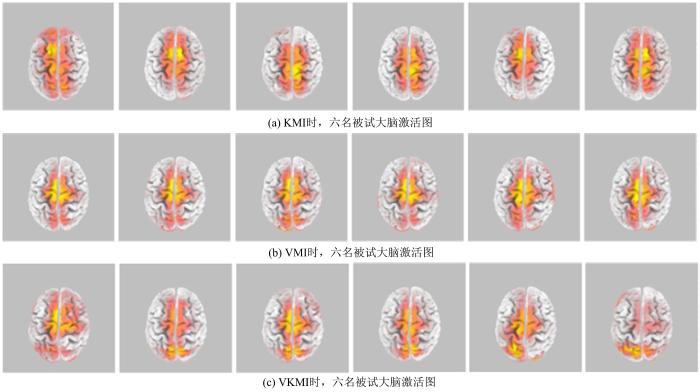

图6 a、图6 b和图6 c分别显示六名被试在KMI,VMI和VKMI下的脑激活图.可以看出被试之间个体差异较小.

图6

六名被试的大脑激活图

Fig.6

Brain activation map of six subjects

在实验2中,通过溯源分析比较了KMI,VMI和VKMI三种不同想象方式下脑区激活数量与激活程度.在想象行走期间,VKMI方式在运动皮层的激活持续时间占比高于VMI方式,在体感皮层的激活持续时间占比高于KMI方式,所以VKMI可能更有利于促进这些脑区的可塑性,对下肢运动功能障碍的康复训练有益.值得注意的是,对于VMI激活的是哪些脑区尚无明确定论,一些研究发现KMI主要激活运动区及其顶叶,而VMI的激活区域在枕叶和上顶叶[25 -26 ] ;另有研究发现KMI与VMI激活的区域在顶叶的重叠度很高[27 ] ,但还有研究得出了不同的结果[28 ] .本研究采用64导溯源分析,得到了与唐万等[23 ] 相似的结果.在实验1和实验3中,还构建了少导联的BCI系统,结果表明其分类准确率优于单一VMI或KMI,而且,采用导联数较少,有利于系统的便携性和实用化.同时,通过图6 的大脑激活图可以看出,六名被试之间的差异性较小.